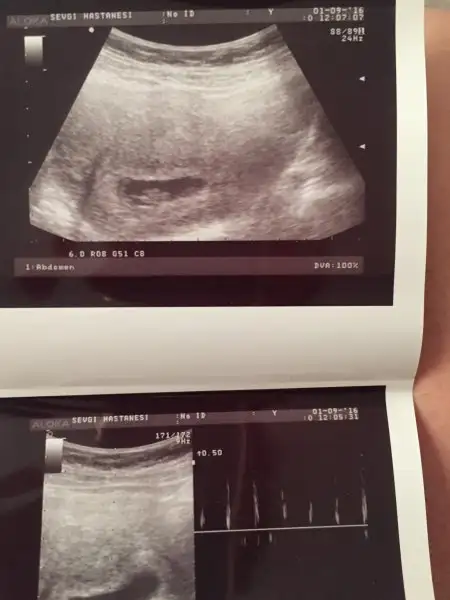

Siz kaç haftalıksınız?Bende öğrenemedim yine

Karından değilUsg karındansa kız gibi,vajinalsa erkek gibi

Benim sağımday dı keseKarından değil

Kız bekliyordumKarından değil

Kese büyük ise kız küçük ise erkek ben geçmiş yorumlarina bakmişim.. doğru mu bilmiyorum. bazilarin tam tersi olabiliyo kişiden kişiye degişiyor.Eki Görüntüle 1879943 Kızlar bilen varsa yorum yapsın bari dundendir bekliyorum son adet tarihine göre 10 + 2 iki gün önce doktora gittim ultrasonda 11 haftalık çıktı

öle oluyormuş fasulye gibiyse erkek yuvarlak ise kızmiş:)Havalianne__ burda benim bebeğim 8+5 haftalık. Kese yuvarlaksa kız fasulye gibiyse erkek miydi. Benimki tam yuvarlak da değil tam fasulyede değil sanki. Ona göre bi bakar mısın